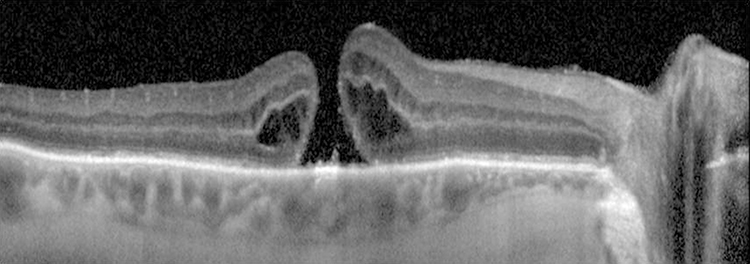

Figure 11.25.2: Optical coherence tomography of macular hole.

A full-thickness macular hole appears as a round, red spot in the center of the macula, usually from one-third to two-thirds of a disc diameter in size; may be surrounded by a gray halo/cuff of SRF. VMT demonstrates loss of the normal foveolar depression and often a yellow spot or ring in the center of the macula.

Small, yellow precipitates deep to the retina in the hole or surrounding retina; retinal cysts at the margin of the hole or a small operculum above the hole, anterior to the retina (Gass stage 3 or 4); or both.